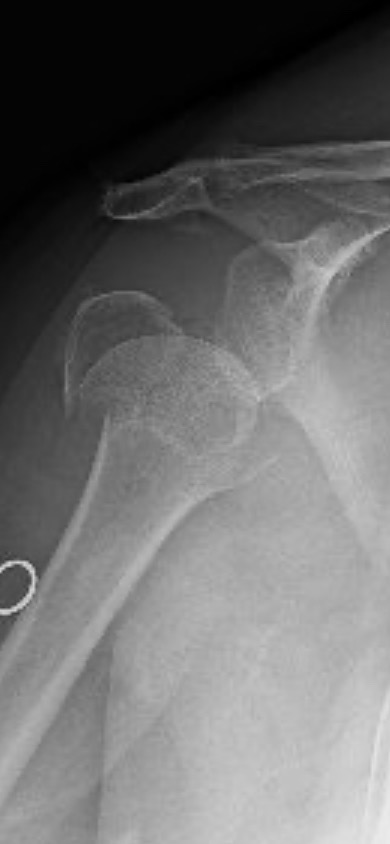

Last Friday morning, what started as a normal day took an unexpected and devastating turn. While walking into a local shop for coffee, I had a fall that resulted in a broken shoulder. I've since learned that the break is severe – into three pieces, with the top part completely detached. I’ve met with an orthopedist to determine the best course of action. The doctor has presented two difficult options:

Reversal shoulder replacement surgery: This comes with a higher risk of complications and may not fully restore the mobility I need.

Letting it heal naturally: This option carries a significant risk but the potential for less mobility, potentially leaving me unable to lift my arm above waist level.

My choice is surgery.